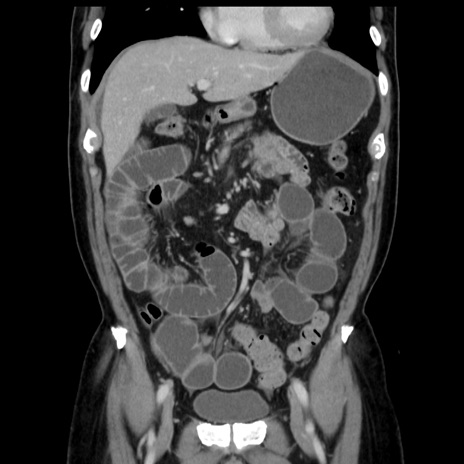

症例16(冠状断像)

【症例】 70歳代男性

【主訴】 腹痛、嘔吐

【現病歴】 約1ヶ月前より間欠的に腹痛と嘔吐あり、当院消化器内科を受診したところCTで多発する肝臓のLDAを指摘され、精査中であった。以降は消化器症状は安定していたが、2日前より嘔気と腹痛があり、同日より排便・排ガスが消失した。改善認めず、 本日、救急外来を受診した。

【既往歴】 大腸ポリープ切除後。

【身体所見】意識清明・会話良好、BT 36.3℃、BP 127/80mmHg、 P 80bpm、腹部:膨満あり、平坦・軟、上腹部正中および下腹部正中に圧痛あり、反跳痛なし、筋性防御なし。

【データ】WBC 7200、CRP 0.77